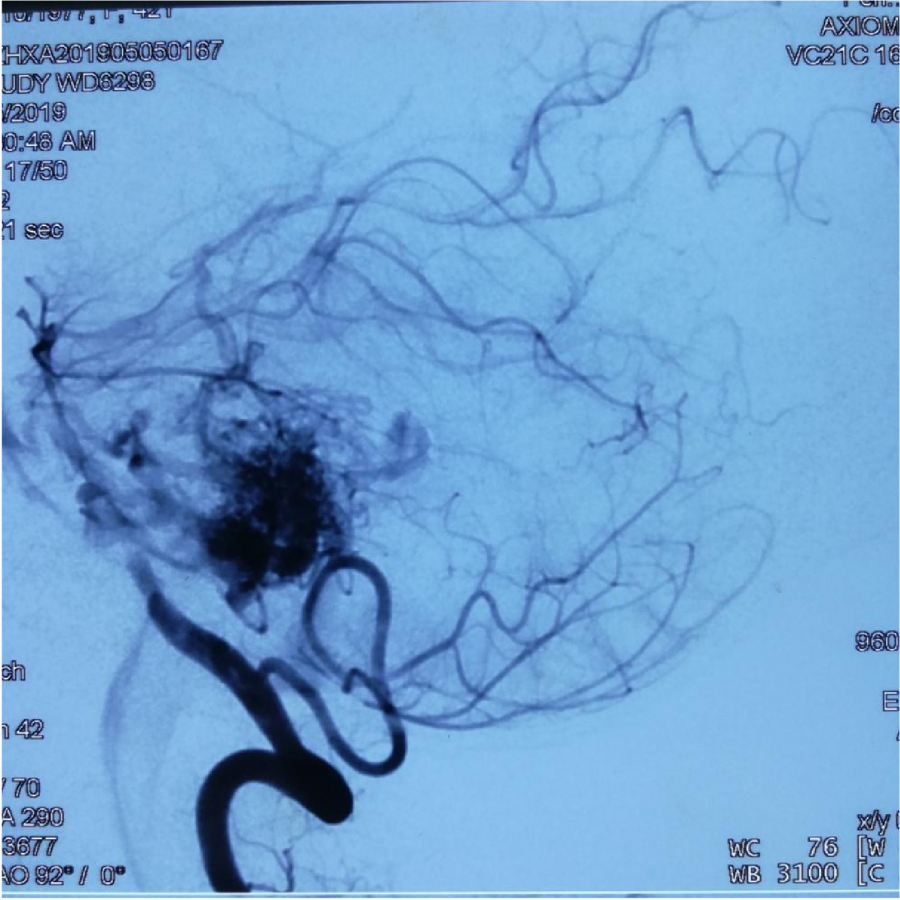

第⼀次DSA显⽰PICA供⾎

引流⾄⼄状窦

小脑后下动脉、小脑前下动脉参与供⾎

颈外动脉造影显⽰枕动脉参与供⾎